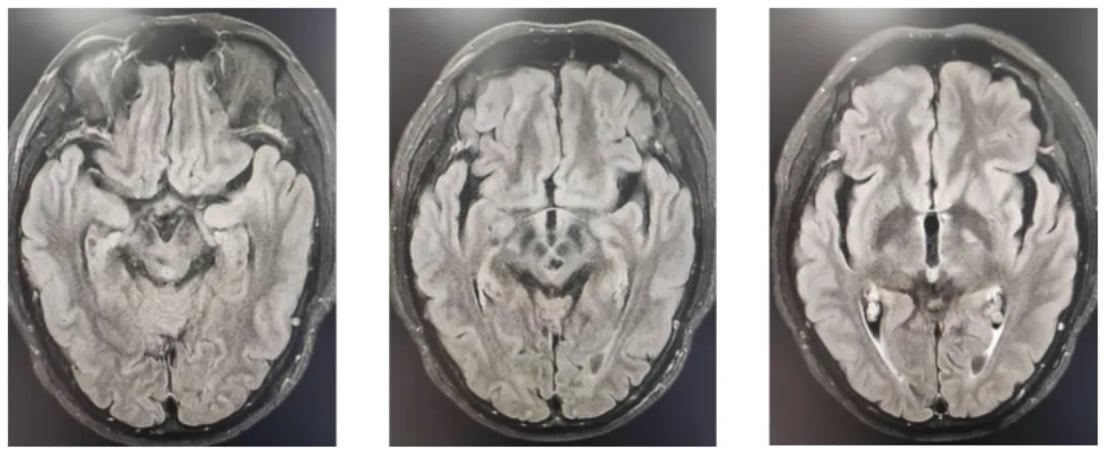

不幸的是,在2024年5月的复查中,MR影像提示部分病灶范围较前增大,表明肿瘤出现进展。面对疾病进展,医疗团队迅速调整策略,为患者制定了再程放化疗方案。此次治疗在放疗的基础上,联合使用了替尼泊苷和替莫唑胺(Temozolomide)两种化疗药物。经过新一轮的同步治疗和后续的维持化疗,患者的病情再次得到有效控制。最近的MR复查结果令人鼓舞,显示病灶范围较前缩小,疗效评价为部分缓解(PR)。

图3 进展前影像学